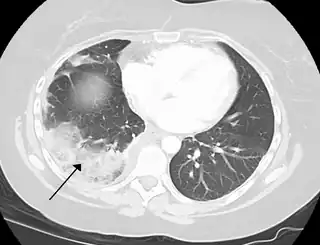

- En el pulmón (Infarto pulmonar).

Si bien la mayoría de los infartos se originan por la obstrucción de una arteria (brazos, piernas, intestino, etc.), los infartos pulmonares pueden ser de origen venoso por cuanto la sangre de la arteria pulmonar procede directamente de la circulación venosa a través de las cavidades derechas del corazón y es capaz de llevar un trombo desde las venas de las extremidades o abdomen a ocluir un vaso arterial pulmonar.